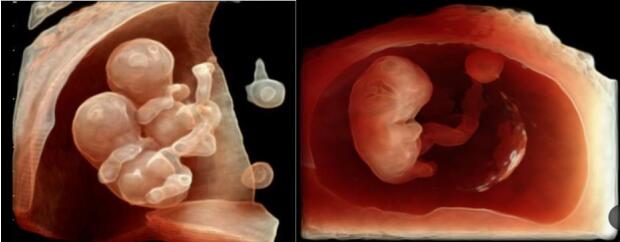

早孕期11周---13周6天

早孕期评估胚胎发育

观察宝宝最初的生长状态,近可能早的判断胎儿畸形

NT/IT的自动测量评估染色体异常